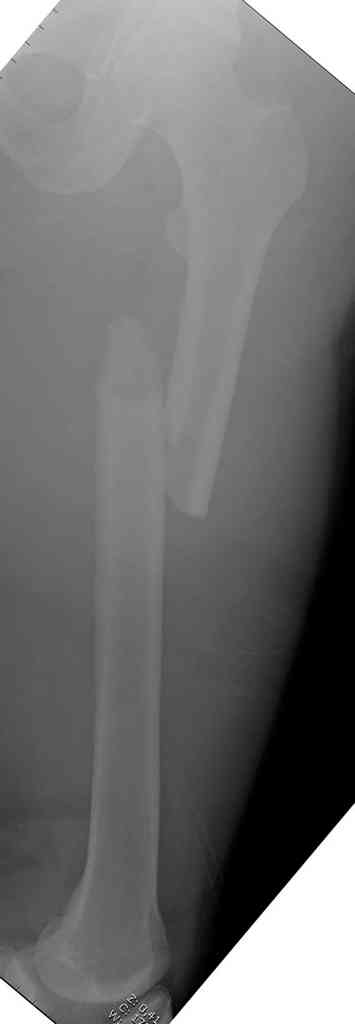

С наступающим Новым 2007 годом! Желаю успехов в работе, здоровья вам, родным и близким.Оперировали диафизарный перелом бедра у тяжелого больного(после АРО, с анемией, с нарушениями свертывания). Снимка В\3 бедра до операции не было, штифт пробит ретроградно без проблем. После операции: гемоглобин 86, прошло 6 дней. Смущала отечность в В\3 бедра, на рентгенограмме вот такая "новость". Как выйти из этой ситуации? Вытащить штифт, посадить пластину на С\3, а на В\3 углообразную пластину после коррекции (остеотомии) не позволяет состояние больного. А есть смысл ввести мимо штифта компрессирующие винты под рентген-контролем? Ваши предложения? Заранее благодарю.

Даже если бы и позволяло состояние больного, делать этого ни в коем случае не надо. Какая коррекция (остеотомия)??? Перелом шейки очень латеральный, практически без смещения, кровообращение головкт бедра не должно было пострадать, возраст, судя по всему, - молодой... Хорошие перспективы для сращения шейки.

Диафизарный перелом простой опорный - должен срастись и на таком неблокруемом гвозде (если туго посажен в рассверленный канал).

ИГД> Снимка В\3 бедра до операции не было,

Мы в год получаем по 3-4 пациента с аналогичной ситуацией - поздно обнаруженный перелом шейки бедра и фиксированный диафизрный. Почему-то часто не делают снимки длинных костей на протяжении, на пленке 15x40 или 30х40 см, любят для всего кассеты 24х30 см. На других сегментах тоже встречаются такие проблемы.

ИГД> на рентгенограмме вот такая "новость".

Это еще относительно рано обнаружили...